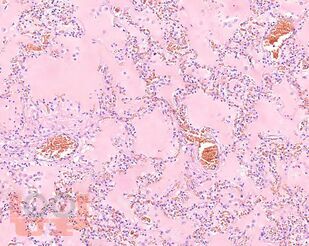

В учебном пособии представлен теоретический материал, перечень макропрепаратов и микропрепаратов, демонстрирующих типовые проявления патологических процессов. В цветных иллюстрациях и в описании микропрепаратов

сделан акцент на наиболее важных гистологических изменениях, позволяющих на светооптическом уровне диагностировать и дифференцировать состояния, отклоняющиеся от нормы, в том числе с использованием различных гистологических окрасок. Пособие помогает выделить главные аспекты изучаемых патологических процессов, организовать и конкретизировать учебный процесс.